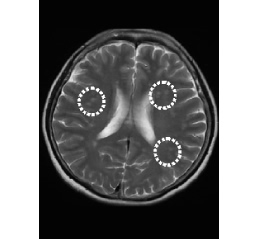

MRI画像

微小脳梗塞

MRI画像

脳梗塞